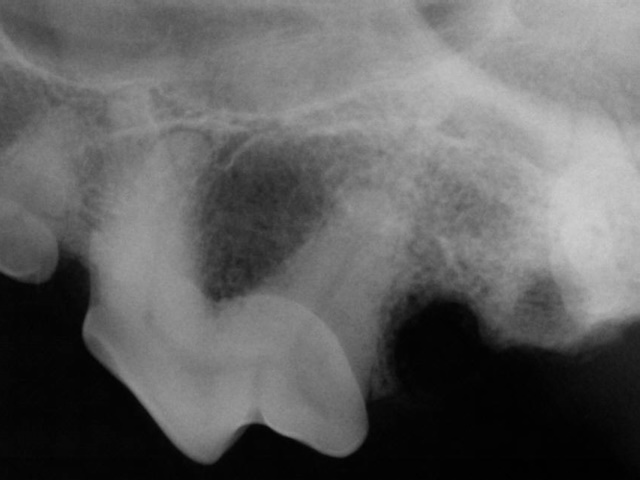

A cavity on the chewing surface of the upper first molar in a dog is seen (blue arrows).

This cavity has created a deep defect and infection in the crown (red arrows) which already spread to the pulp and the bone around the root tip (yellow arrows).

This tooth was deemed structurally irreparable, and it was extracted to get rid of the infection. Extraction site healed well in a month.

Post-extraction dental radiograph shows complete extraction of all the roots.